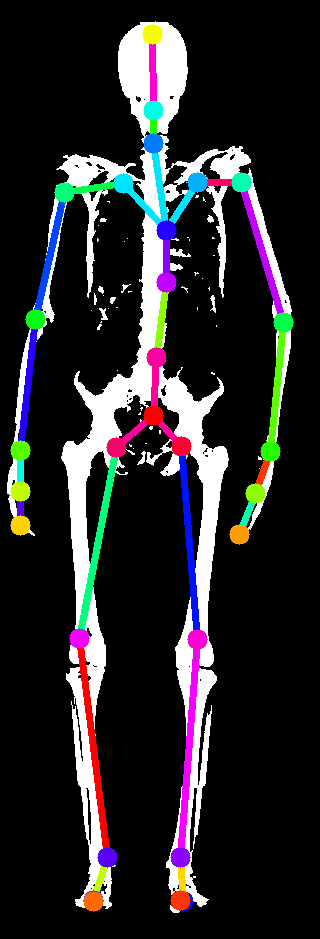

In this work, we address the problem of inferring the human anatomic skeleton, i.e. the bone shapes and locations, solely from surface observations. That is, we infer the bones from the skin. To that end, we learn a statistical model of the skeleton shape and its correlation with the skin surface (Fig. 1 left). Given a posed body, our method predicts the skeleton from the body shape, and poses it inside subject to anatomic constraints (Fig. 1 right).

5.4 Generalization to new poses